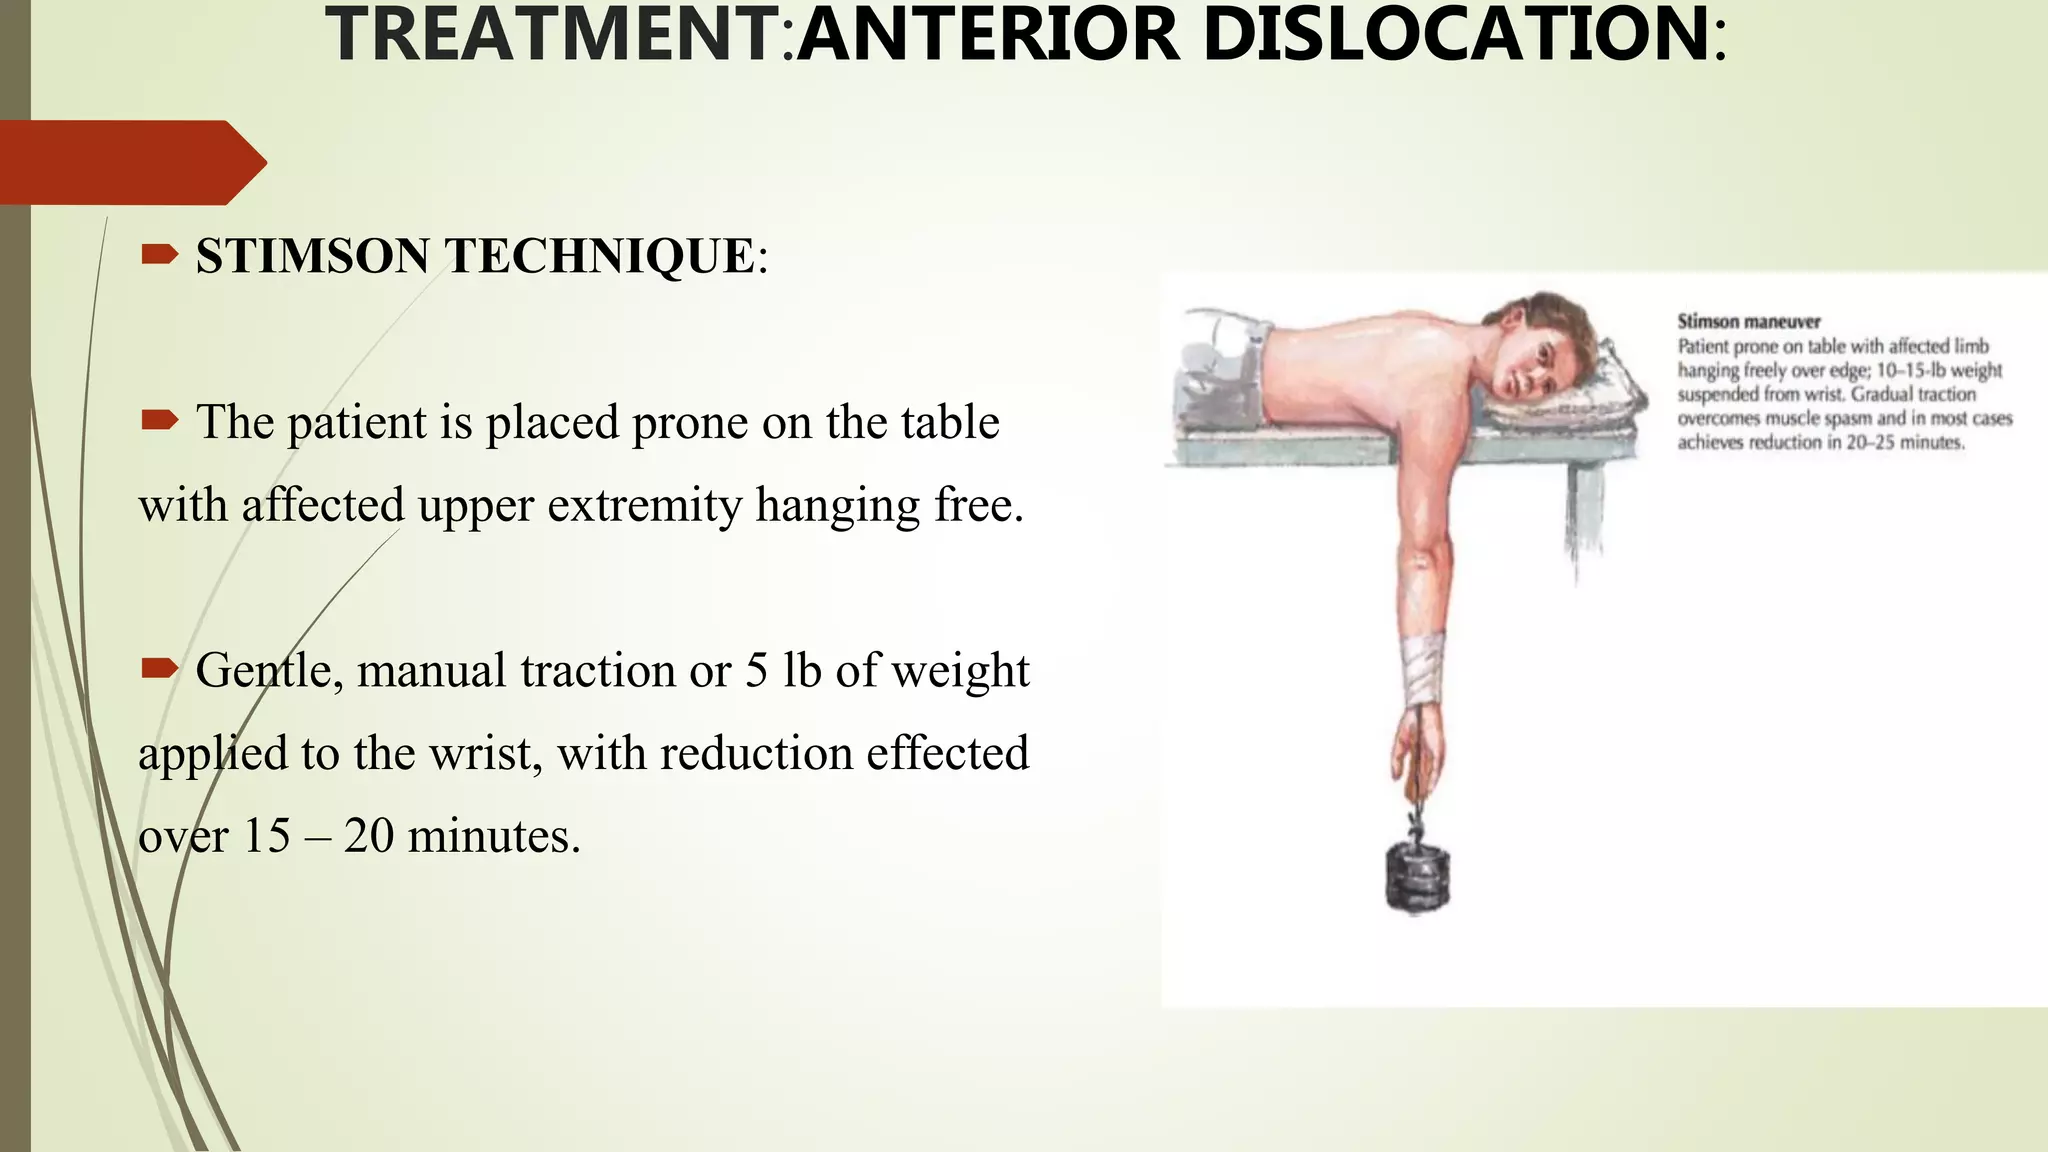

- Treatment involves closed reduction for most acute dislocations. Recurrent or complicated dislocations may require surgery and immobilization followed by physical therapy.